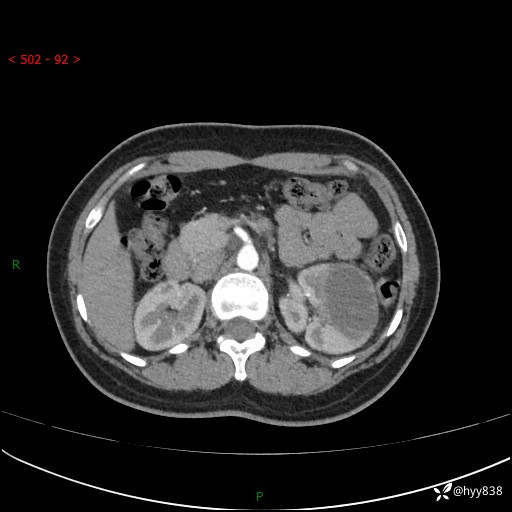

现病史:患者于1周前因左侧腰腹部间断胀痛不适,无恶心呕吐,无明显肉眼血尿,无畏寒发热,无尿频尿急,起病初,患者来我院就诊,查CT提示左肾低密度影,外周血提示:白细胞11.25*10^9/L.行抗感染治疗后未见明显好转,06-18泌尿系增强CT提示左肾类圆形低密度占位(脓肿?肿瘤?),大小:4.0*3.2cm,为求进一步治疗,门诊以“左肾占位”收住我科。 起病以来,患者精神佳,饮食、睡眠良好,大小便正常,体力体重无明显变化。

双肾CT平扫+增强